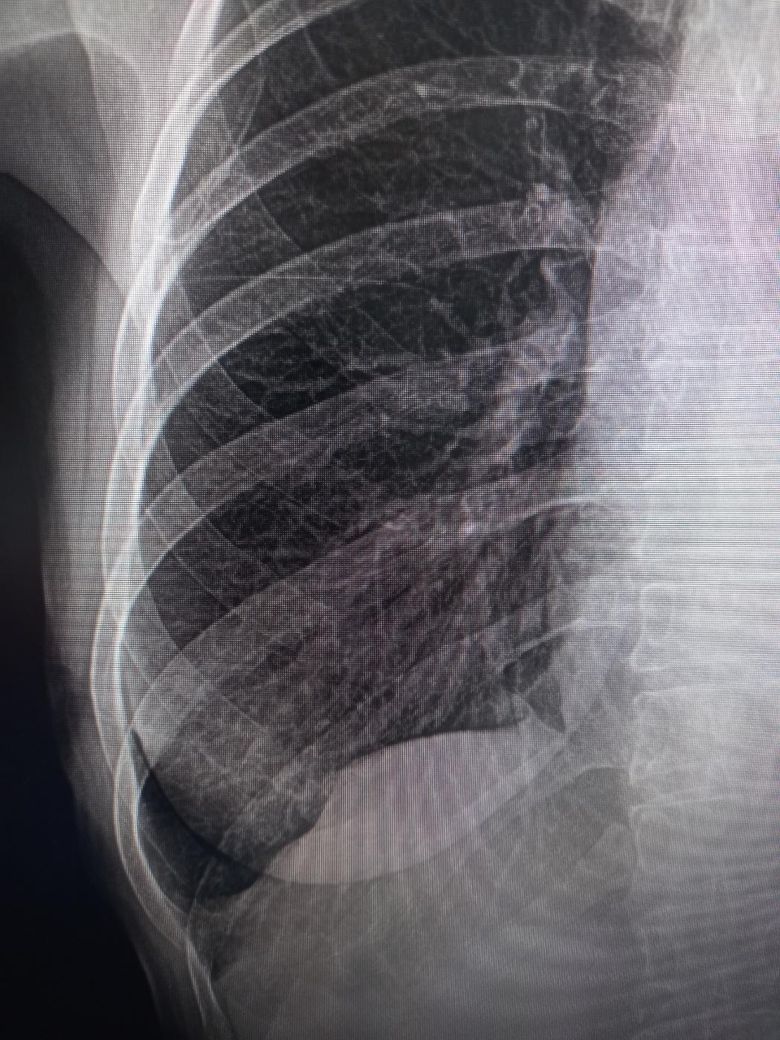

72세 흉부 엑스레이 사진 봐주세요.

전후 사진입니다. 전 사진은 약 1년전 사진이고요 오늘 찍은거랑 비교해봤을때, 선생님께서 우측 하복부 늑막변형 소견이라 큰병원가서 흉부CT찍어보라는데요 위암1기 (1기중에서도 초기) 전절제 한지 18개월차인데 전이일 수 있나요? 평상시 통증이나 체력 저하 등 달라진건 전혀없으시고 식사,운동 잘하십니다

• 1번 째 사진

모니터를 핸드폰으로 찍으셨는지 올려주신 사진의 경우 해상도가 떨어집니다.

우측 하복부 늑막변형 소견에 대해서는 좀 더 자세한 검사를 위해 흉부CT 검사를 권합니다.

초기 위암 병변을 전절제 한 경우 위 내시경 검사의 확인이 필요하겠으나 전이 가능성은 낮을 것 같습니다.